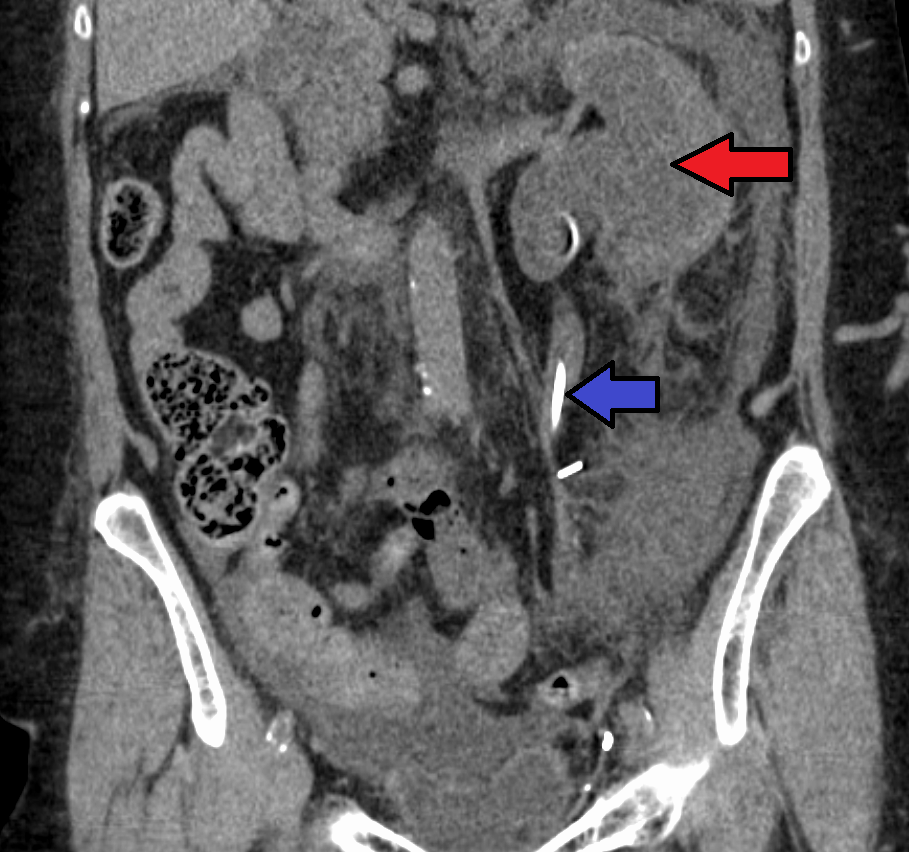

수신증은 신장, 요관, 방광 사이의 연결 부위의 구조적 이상, 신장 결석, 전립선 비대증 등 다양한 원인으로 인해 신장 내 소변이 제대로 배출되지 못하고 축적되는 질환이다. 수신증은 급성 또는 만성으로 나타나며, 증상은 통증, 메스꺼움, 구토, 요로 감염, 신부전 등 다양하다. 진단은 초음파, CT, MRI 등의 영상 검사, 혈액 및 소변 검사를 통해 이루어지며, 치료는 폐색을 제거하고 소변 배출을 원활하게 하는 데 중점을 둔다. 예후는 원인, 범위, 기존 신장 기능 등에 따라 다르며, 장기간의 수신증은 영구적인 신장 손상을 유발할 수 있다.

질병을 진단하려면 환자의 병력과 기타 신체 검사 정보를 알아야 한다. 이는 일부 영상 검사를 동반해야 한다. 일반적으로 초음파 검사를 사용하여 환자의 요로, 콩팥 등의 상태를 확인할 수 있다. 또한 CT 스캔과 MRI는 요로 및 폐쇄를 보다 명확하게 보여줄 수 있다.[8]

정맥 신우 조영술(IVU), 신장 초음파 검사, CT, MRI 등의 영상 검사도 중요하다. 초음파 검사는 요관과 신장을 시각화하고 수신증 및 수뇨관증 유무를 확인하는 데 유용하며, IVU는 막힘의 해부학적 위치 평가에 유용하다. 순행 또는 역행 신우 조영술은 IVU와 유사한 소견을 보이면서 치료 옵션도 제공한다. 실시간 초음파와 도플러 초음파 검사는 혈관 저항 검사와 함께 폐색이 요로 기능에 미치는 영향을 파악하는 데 도움이 된다.[12]

신 산통(소변에 혈흔이 섞인 옆구리 통증)의 초기 검사는 나선형 또는 헬리컬 CT 스캔이다. 이는 소변 흐름 폐색 여부와 다른 신장 기능도 보여준다. CT는 대부분의 결석을 확인할 수 있어 초기 검사로 흔히 선택되지만, 임신과 같이 방사선 노출을 피해야 하는 경우에는 사용하지 않는다.[13][14] 우연히 발견된 산전 수신증의 경우, 첫 검사는 산후 신장 초음파 검사다. 산전 수신증의 많은 사례가 자연적으로 해결되기 때문이다. 출생 후 며칠 이내에 시행하지만, 너무 이른 검사는 경미한 수신증을 놓칠 수 있어 4~6주 후 추적 초음파 검사를 권장하기도 한다.[15] 배뇨 방광 요도 조영술(VCUG)은 방광 요관 역류나 후부 요도 판막 같은 해부학적 이상을 배제하기 위해 시행된다. 수신증이 심각하고 요관 신우 접합부(UPJ) 또는 요관 방광 접합부(UVJ) 폐색이 의심되면, MAG-3 스캔과 같은 핵 영상 검사가 필요하다.[13]